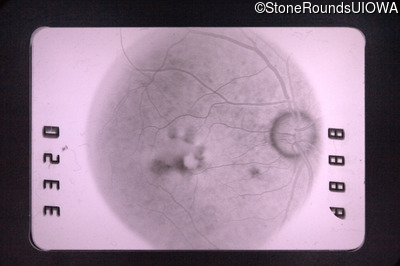

Fluorescein Angiography - Right - 20/70 -1 cc

Exemplar